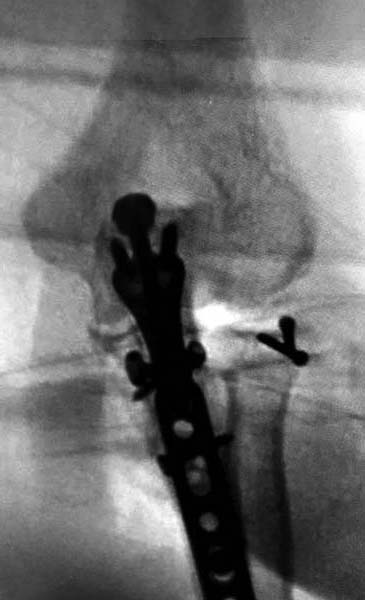

Конверсионные спицы на уровне проксимального отдела лучевой кости

интересная идея, но на уровне перелома в области шейки трудно удержать

головку. Предварительная репозиция локтевого отростка с временной

установкой пластины, затем удаление экономит время. Доступ через

локтевой отросток, где можно фиксировать или удалить головку с

замещением, а потом установить пластину обратно на локтевой отросток!